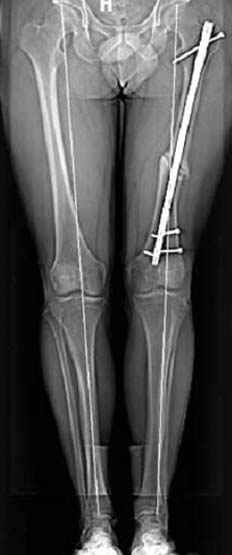

N3 рисунок окончательный снимок, после операции моя рентгенограмма должен выглядеть примерно как эта картина. На N4 снимке клин перед удалением; N5 послеоперации 3 нед.; N6 окончательная рентгенограмма.

Отправитель: Djoldas Kuldjanov 23 Ноябрь 2004, 18:21

пластическая модель; и коррекция бедра аппаратом Илизарова.